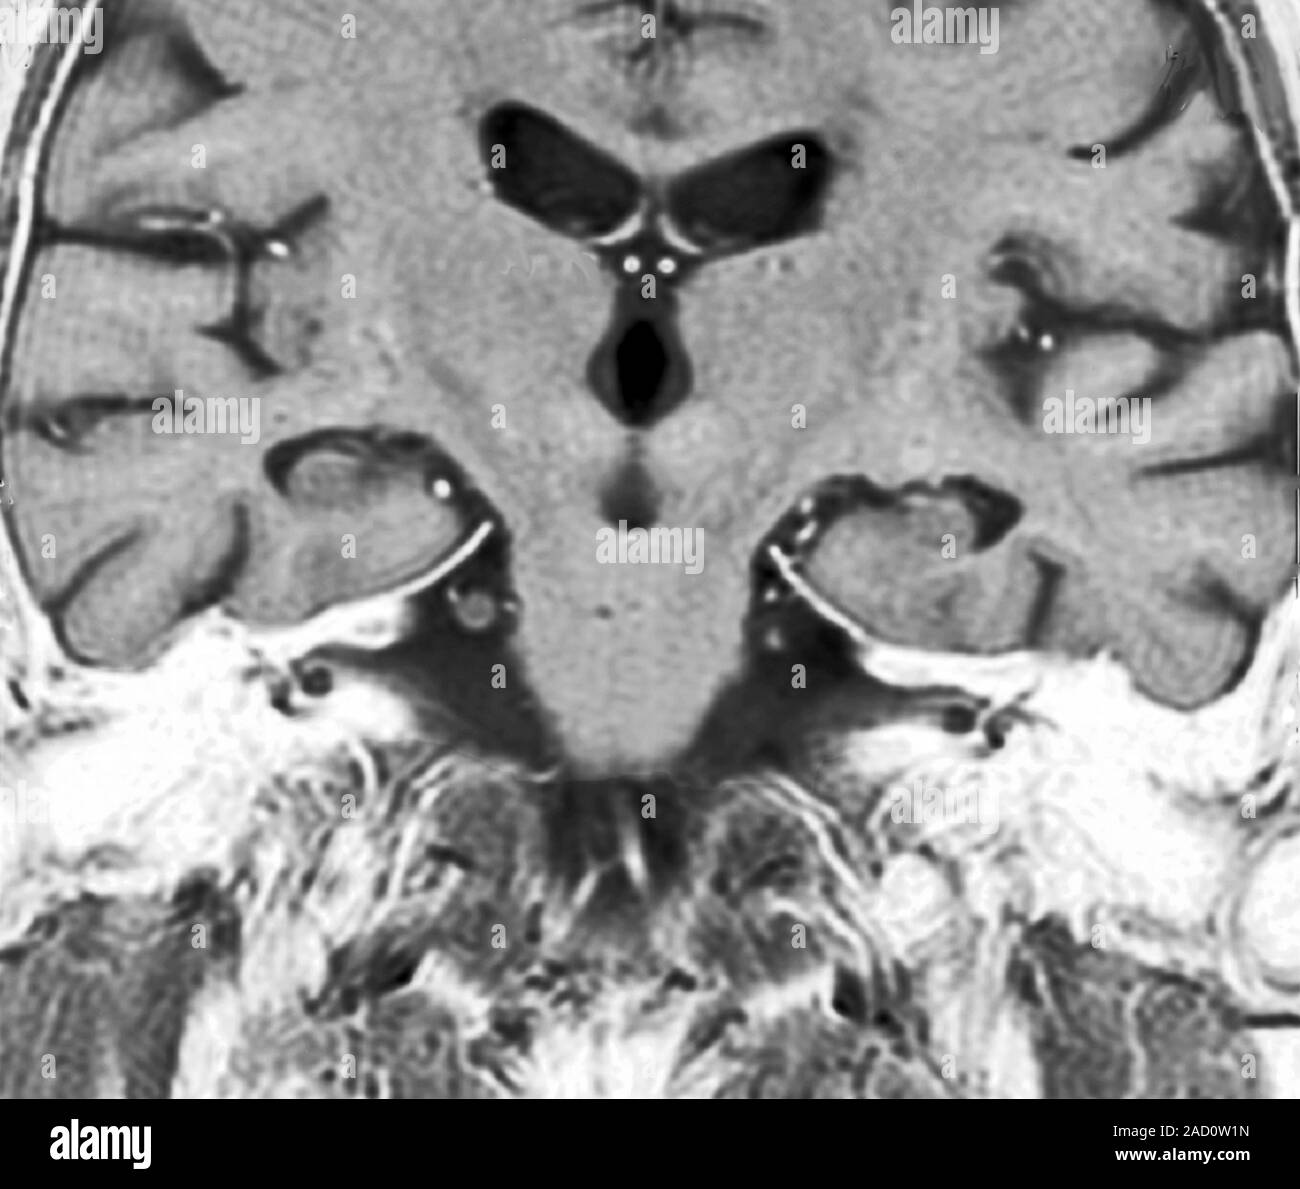

Brain and hippocampus. resonance imaging (MRI) scan of a Coronal Mri Hippocampus (1) a memory impairment is usually the earliest and most. The rationale for quantitative mri of mtl atrophy in the diagnosis of ad is: At mri, the hia refers to the laminar appearance of gray and white matter on coronal sections, with clear differentiation of all segments of the cornu ammonis and the. Mri is the imaging modality of choice. Coronal Mri Hippocampus.

Coronal T2 weighted resonance image of the brain The BMJ Coronal Mri Hippocampus At mri, the hia refers to the laminar appearance of gray and white matter on coronal sections, with clear differentiation of all segments of the cornu ammonis and the. With uhf magnetic resonance imaging (mri), the quantification of subtle differences in hippocampal strata, such as. This study aimed to introduce and categorize various acute conditions that can involve the hippocampus. Coronal Mri Hippocampus.